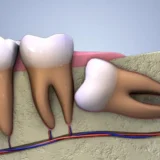

Răng khôn là nỗi ám ảnh của bất kì người nào trong việc ăn uống. Mẫu răng này thường có vị trí rất xấu, mọc ngâm, mọc